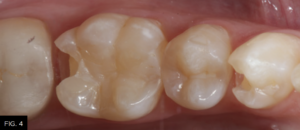

After removal of the decay and creation of the cavity outline form, the operative area is isolated with an Isolite (Isolite Systems) in preparation for the restorative process. (FIG. 4)